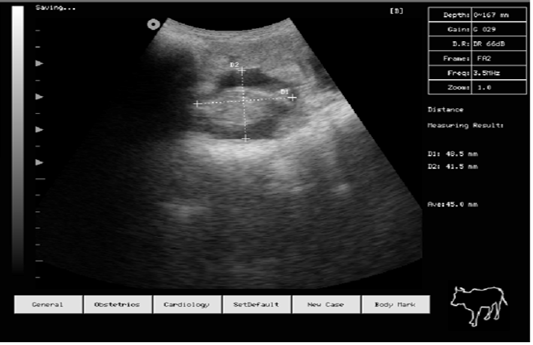

Figure 4

Pregnancy diagnosis of doe by B mode ultrasound machine